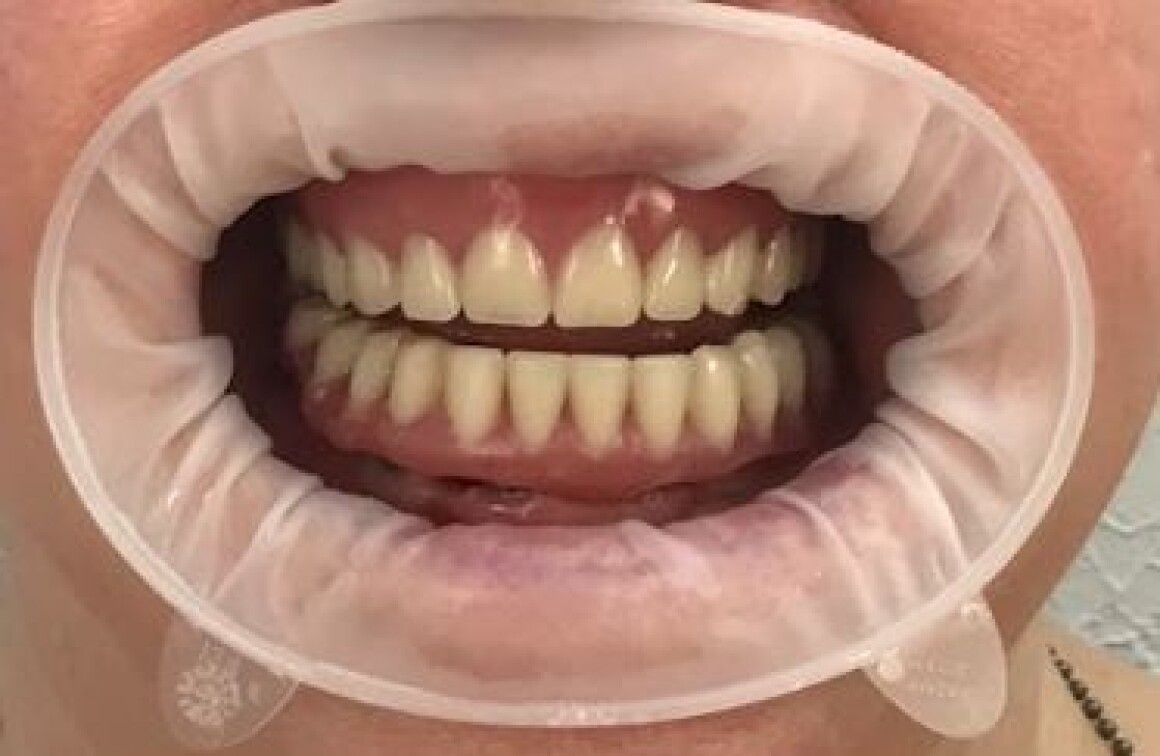

Имплантация и лечение от Александра Сергеевича

Тотальная реабилитация

Проблема : Полное отсутствие зубов, не держаться протезы

План лечения

• Планирование имплантации

• Изготовление временных конструкций на имплантантах

• Изготовление шаблонов для операции

• Имплантация 12 имплантантов за один раз

• Установка временных коронок на имплантантах

• Установка постоянной конструкции из металлокерамики верх и низ

• Общая стоимость

720 900 Р

• Срок

5 месяцев

• Гарантия

12 месяцев